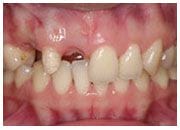

治療前

植入植體

治療後